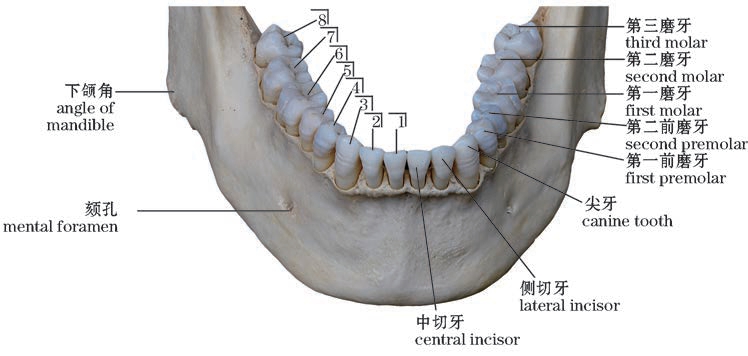

图4-9 下颌恒牙(前上面观)

The permanent teeth of the mandible(Anterosuperior view)